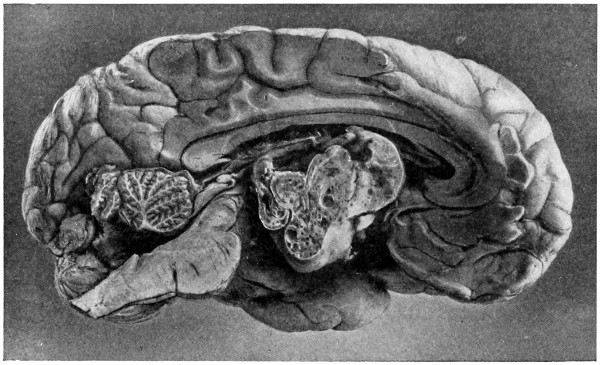

The child was 3 months old, and presented a tumour, the size of an orange, situated between the occipital protuberance and the nape of the neck. The mass was pedunculated, the stalk being about the size of a four-shilling piece in diameter. It was soft, translucent, irreducible, and swelled up on coughing. An attempt at removal was carried out, and, after incising the outermost layers, three ounces of cerebro-spinal fluid escaped. A second tumour was then found occupying the base of the swelling. This was also punctured, more fluid escaping. Both sacs were cut away and the wound sewn up. Death occurred on the third day, preceded by convulsions, retraction of the head and neck, and high fever. The autopsy showed that the fontanelles were widely open, the anterior measuring 4 inches from side to side and 21⁄2 from before backwards. The bones of the vault were markedly thinned. In the subdural space there was a quantity of fluid, and the cerebral substance was soft and diffluent, the convolutions flattened, and the ventricles distended. There was a broad gap in the occipital bone, extending downwards into the foramen magnum, and in this situation the cerebellum had bulged backwards into the protruding mass. (See Fig. 22).